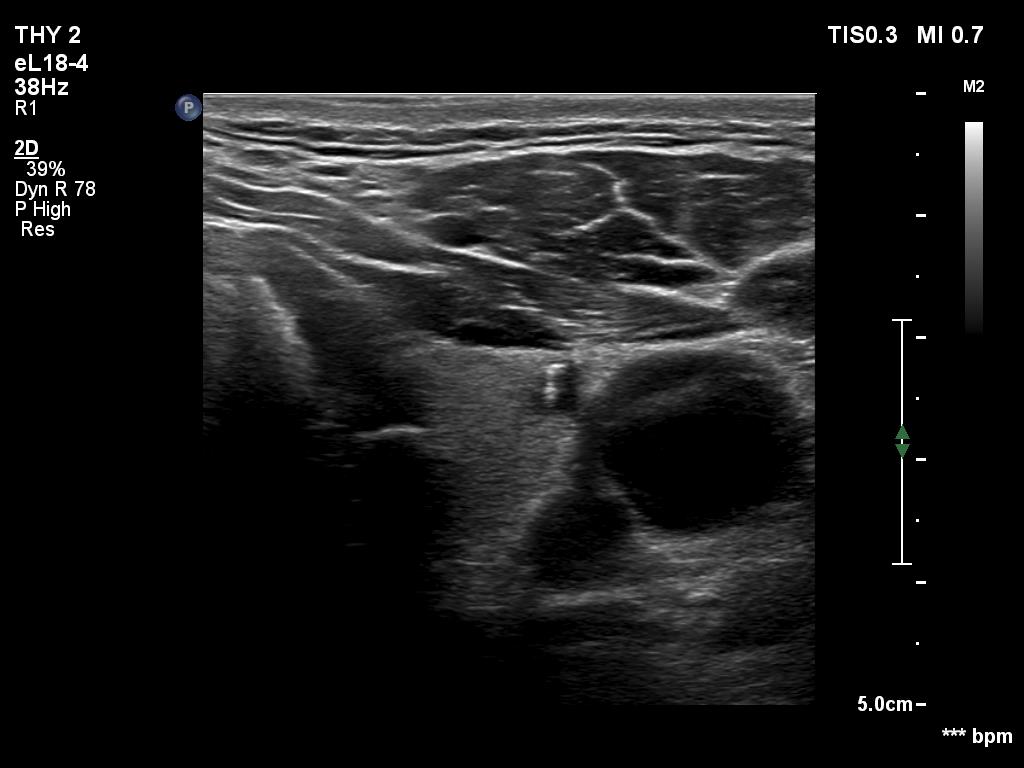

Right lobe, longitudinal scan

Upper part of the left lobe, transverse scan. This tiny cystic lesion has a large comet tail artifact.